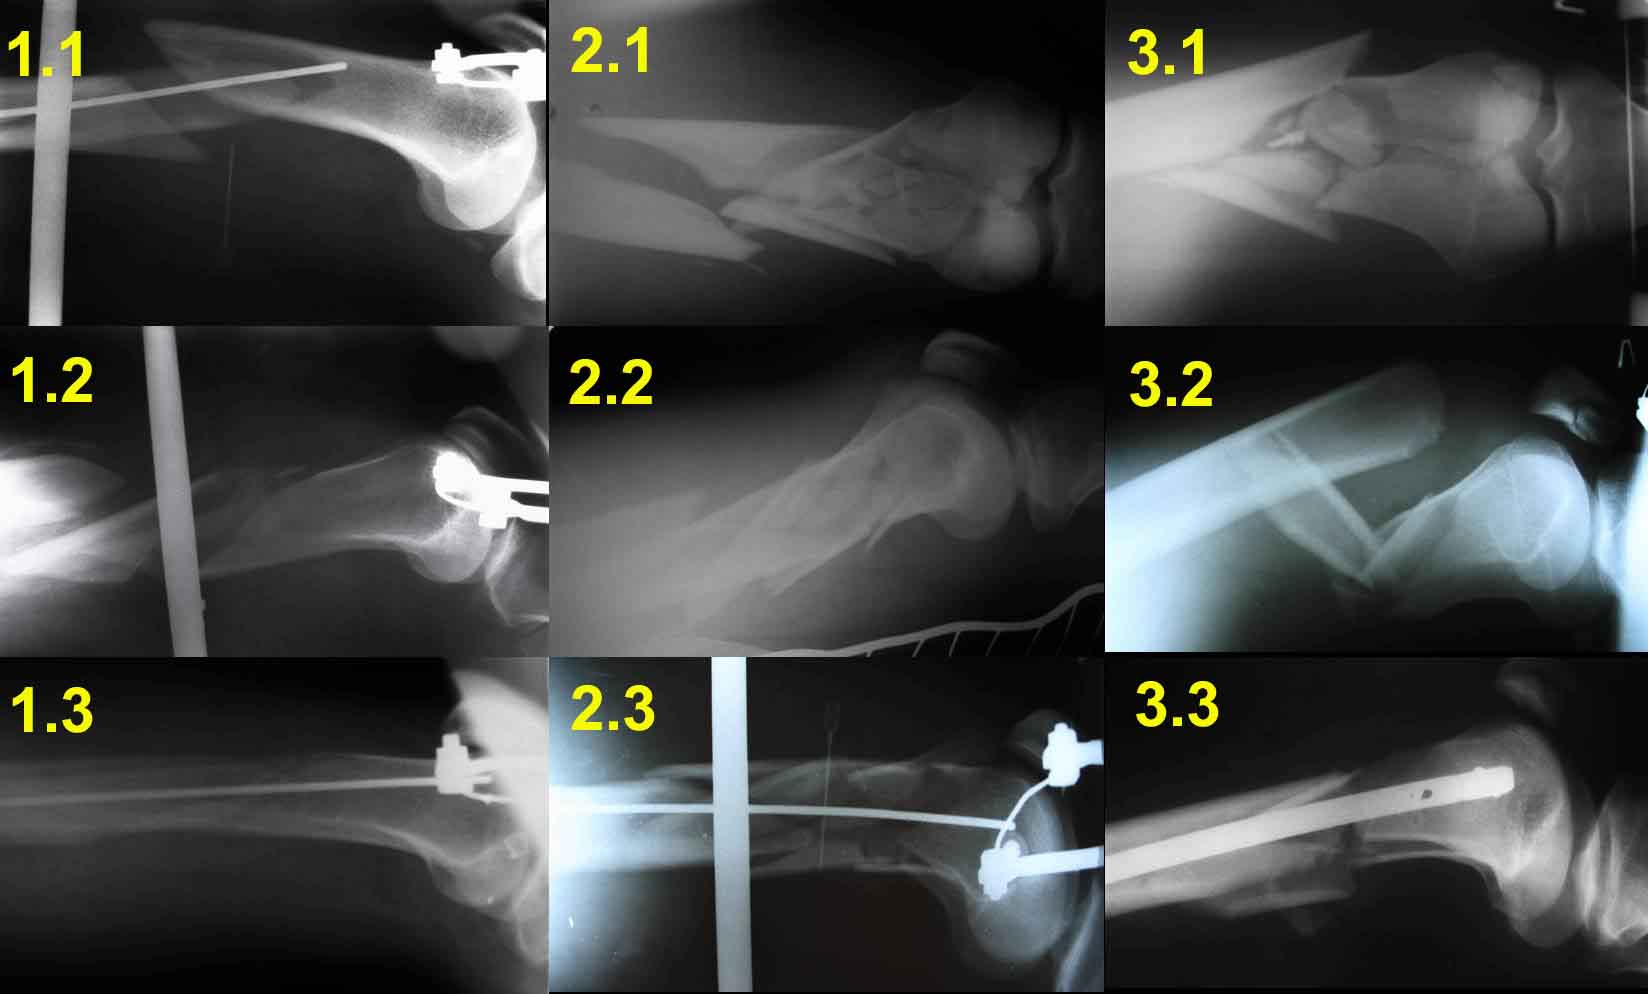

Для примера – вложенный файл.

1.1     – спица проведена сразу за передним кортикальным слоем дистального отломка, поэтому при дистракции появляется задний угол.

1.2      - спица проведена на линии середины диафиза бедренной кости, что привело к передней угловой деформации

1.3      - спица проведена в механически обоснованной точке (0,5 – 0,7 см дорсальнее передней поверхности кортикального слоя), что привело к репозиции костных отломков и ликвидации угловых деформаций.

2.1 -2.3 и 3.1 – 3.3 служат подтверждением того, что любую угловую деформацию при коротком дистальном отломке можно весьма просто устранить, правильно расположив спицу цуг-аппрата.